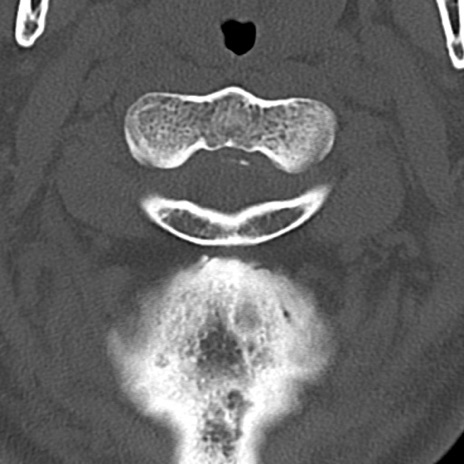

頚椎CT

横断像